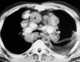

Para-aortic lymphadenopathy